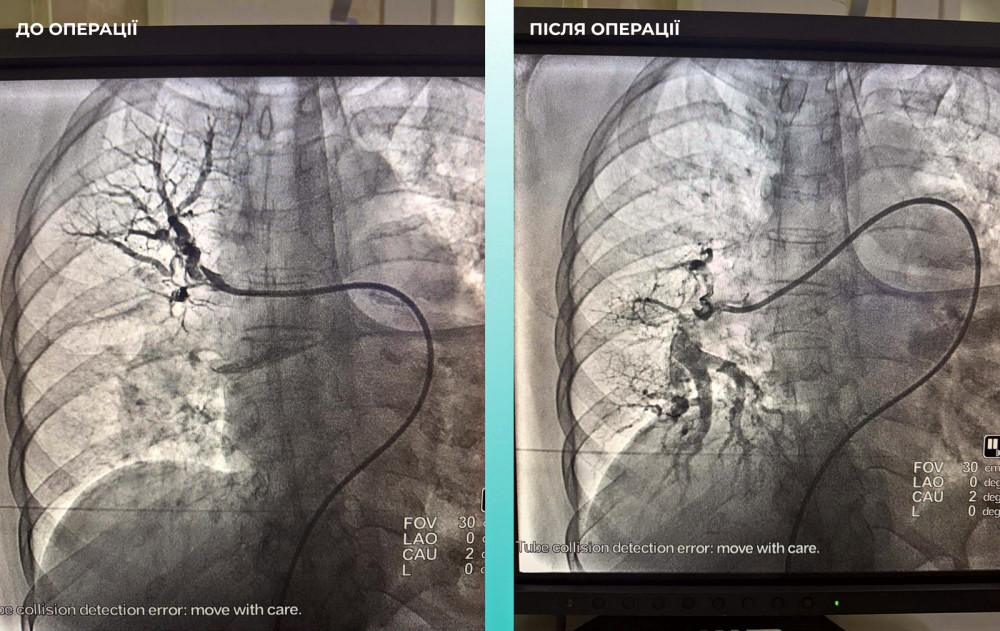

Діагноз ускладнився тромбоемболією, що спричинило необхідність в терміновому втручанні.

Команда спеціалістів вирішила провести операцію, яка об’єднала в собі лікування обох станів одночасно.

Операція виявилася успішною, і пацієнтка почала відновлюватись, демонструючи позитивні результати.